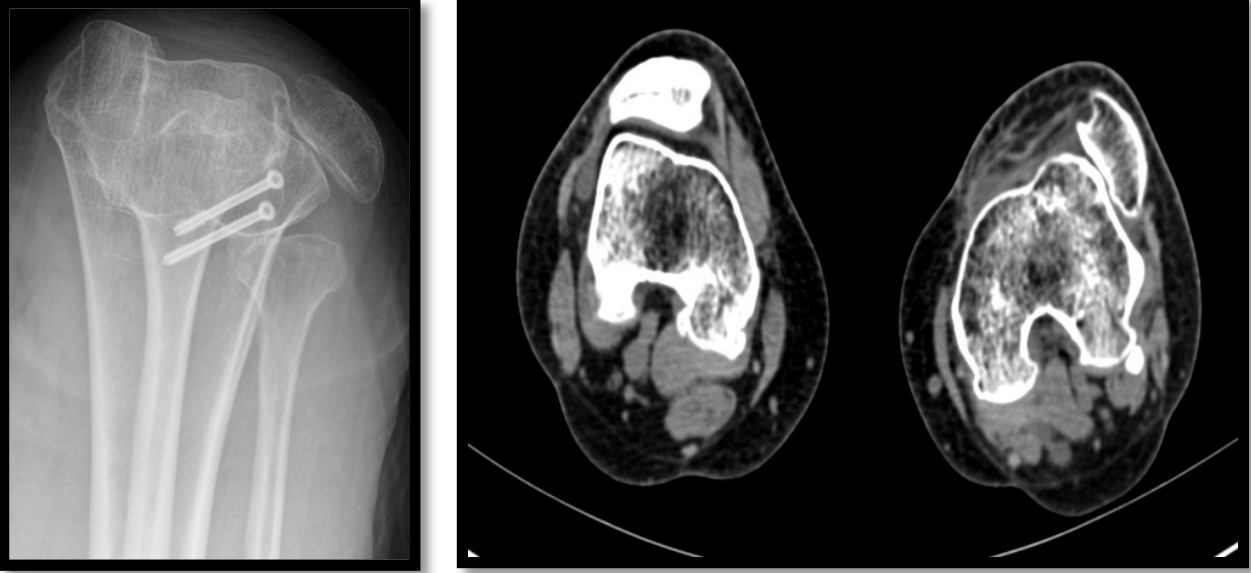

【影像学检查】

【诊断】左侧髌骨固定性脱位